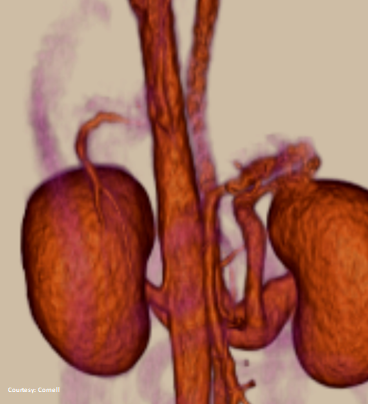

INTRAHEPATIC ENTRANCE

WEISSE 2022